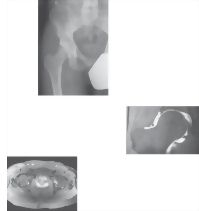

Hip Radiograph, Arthrogram, MR and PETCT Fusion